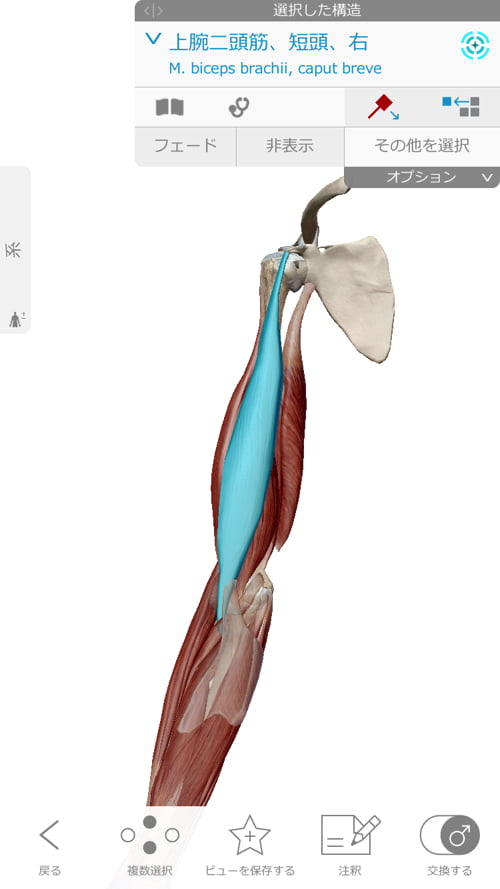

顎下から鎖骨、そして肘に向かうラインに硬直やヨジレが集中しています。

肘や脇、鎖骨、胸付近の筋肉が硬直していて

腕を上げる際に伸び代が無く、腕が上げられない。

施術は肘の硬直と捩れの調整から行います。

肘に硬直やヨジレがあると、こんな感じで繋がっている肩や肩甲骨が

下に引っ張られてズレたり、動かせなくなったりします。

そして胸周りから上腕をしっかり調整。